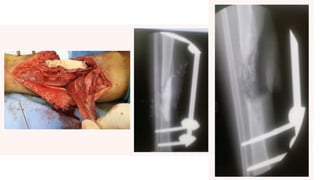

• 12.

Masquelet technique • Primaryshortening followed by lengthening is favoured • Area of segmental loss is filled with a PMMA cement • At 4 to 6 weeks, when an osteogenic membrane has been formed around the cement, the membrane is surgically reopened, the cement is removed, and generous cancellous grafting is carried out • Healing generally occurs slowly but usually by 3 to 6 months. • This, of course, is done in conjunction with internal stabilization. • The membrane itself serves to contain the graft, prevent fibrous ingrowth, and provide growth factors (BMP)